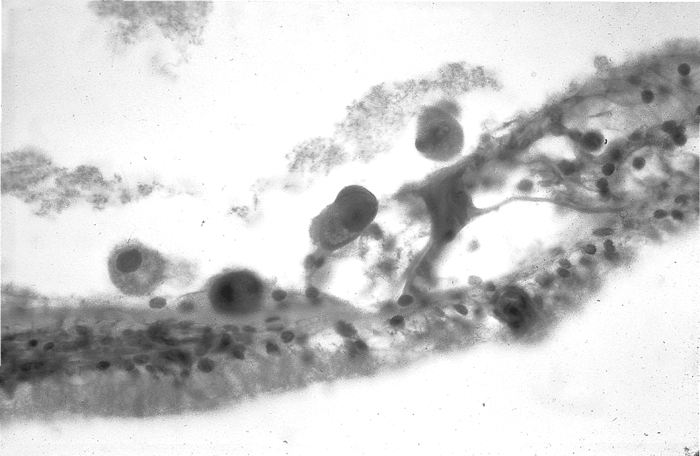

The exact mechanisms of the SNHL, its onset and progression are unknown, but the virus and its effects are seen throughout the cochlear and vestibular structures on temporal bone biopsy, as are inflammatory cells (see Figure 3).

Figure 3: Large CMV infected cells in the organ of Corti courtesy of Professor Leslie Michaels.